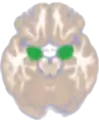

Amygdala along with other subcortical regions, in glass brain. Dorsal view of the amygdalae in an average human brain

Dorsal view of the amygdalae in an average human brain Frontal view of the amygdalae in an average human brain

Frontal view of the amygdalae in an average human brain Left lateral view of the amygdala in an average human brain

Left lateral view of the amygdala in an average human brain Amygdala highlighted in green on coronal T1 MRI images

Amygdala highlighted in green on coronal T1 MRI images Amygdala highlighted in green on sagittal T1 MRI images

Amygdala highlighted in green on sagittal T1 MRI images Amygdala highlighted in green on transversal T1 MRI images

Amygdala highlighted in green on transversal T1 MRI images